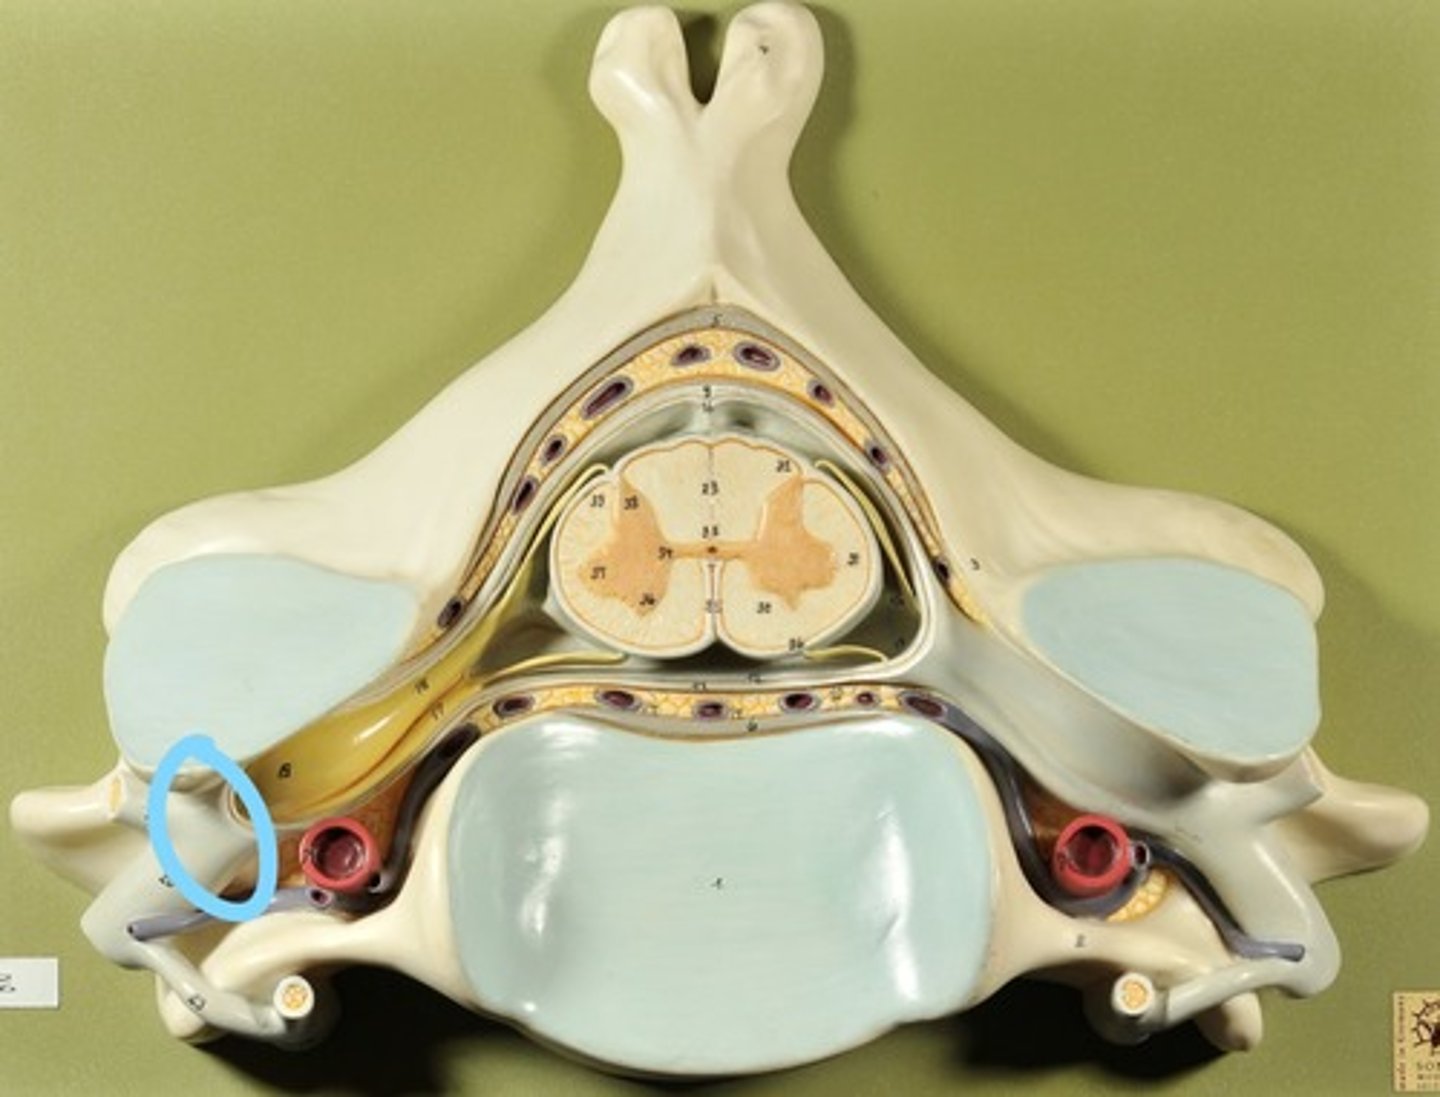

Identify all structures of spinal cord

White Matter of spinal cord

gray matter of spinal cord

Ventral Horns (gray matter)

Lateral Horns (gray matter)

Dorsal horns (gray matter)

Anterior Columns (white matter)

Lateral Columns (white matter)

Posterior Column (white matter)

central canal of spinal cord

Identify all structures

Pia Mater

Subarachnoid Space

Arachnoid mater

Subdural Space (brown line)

Dura mater

Epidural Space

Dorsal Root Ganglion

Dorsal Root

Ventral Root

Spinal Nerve